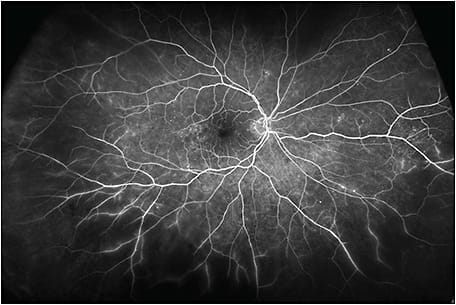

This patient was imaged with the Optos California UWF imaging device, which provides nonmydriatic panoramic fundus images with a 200° view of the retina, displaying 82% of retinal surface area in a single capture. Ultrawidefield fluorescein angiography (UWF-FA) showed microaneurysms and mild leakage at the posterior pole, and identified large areas of peripheral retinal nonperfusion (Figures 2 and 3). Given these results, the severity of this DR changed from mild to severe NPDR. The management was changed accordingly from follow-up to panretinal photocoagulation (PRP).

In this case, UWF fundus imaging enabled the detection of key lesions indicative of DR and large areas of retinal ischemia outside the 7F boundary. Based on the traditional grading scale, the severity of this case had initially been underestimated. However, UWF-FA data graded this DR as severe NPDR, which led to earlier treatment and closer follow-up.